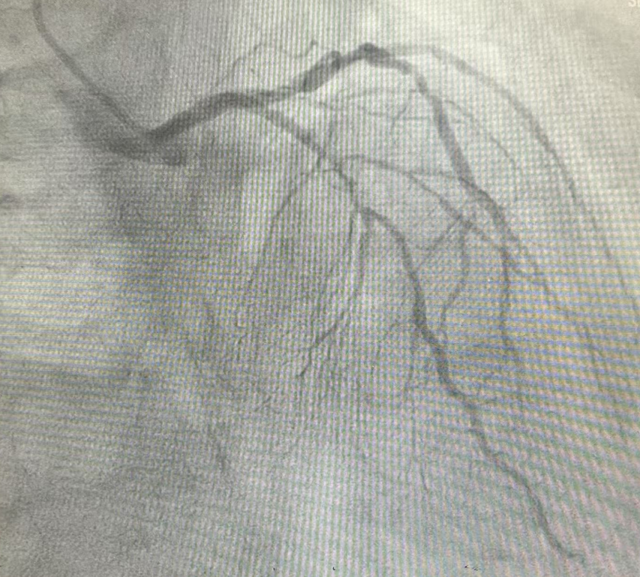

前降支病变血管术前术后图像对比

前降支(LAD)是心脏最重要的供血血管之一,被称为“生命的主干道”。心脏康复科团队在细致评估后,决定采用冠脉支架植入术为王大爷进行治疗。术中通过桡动脉入路,将导丝精准送至LAD病变部位,利用球囊扩张狭窄处后,成功植入一枚药物涂层支架。支架释放后,血管狭窄处立即得到扩张,完善造影示支架贴壁良好,TIMI 血流三级。手术全程仅用时40分钟,创伤小、恢复快。术后患者胸闷、憋气症状显著缓解,生活质量大幅提升。